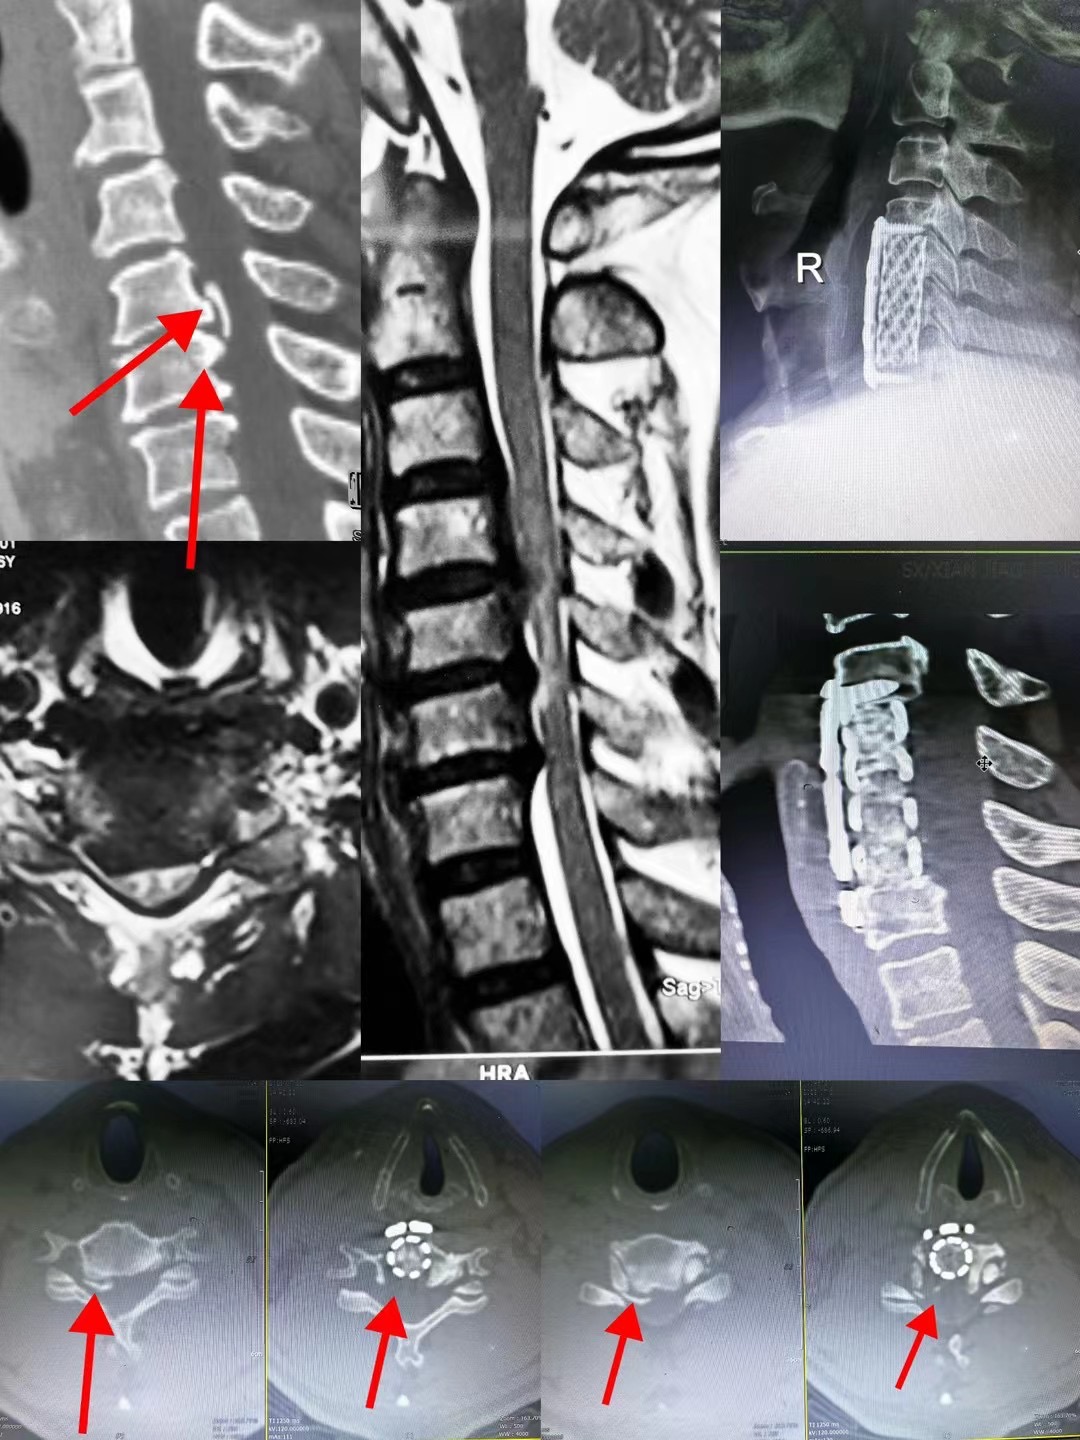

近日,骨二科臧全金副主任医师团队成功完成一例复杂脊柱手术。患者为颅底凹陷症合并脊柱侧凸,已经在西安多家医院门诊就诊,并在某知名三家医院住院治疗,但均未获得良好诊治。后来在北医三院主任医师推荐下来到臧全金副主任医师处治疗。接诊后,臧全金发现患者为严重的颅底凹陷症合并脊柱侧弯,实属罕见,治疗难度大,风险高。但正是这样的病例激起了他的兴趣,术前其带领的治疗团队详细研读了患者的影像资料,制定了详尽的手术方案,于近日一期完成了颅底凹陷症的解剖复位和脊柱侧凸截骨矫形术,术后患者恢复良好,无任何神经并发症。颅底凹陷症合并寰枢椎脱位、脊柱侧凸两种疾病任何任何一种在脊柱外科都属于高难度复杂手术,在脊柱外科领域都属于珠穆朗玛峰般的存在,西北地区只有少数几家三甲医院开展此类疾病的手术治疗,而能够主刀完成这种手术的医生少之又少。看到孩子顺利完成手术,患者家属感到特别高兴,再三感谢臧全金副主任医师团队高超的手术技艺以及过人的胆识,为自己的孩子解决了困扰多年的疾病。

像这样的高难度颈椎手术,臧全金副主任医师带领曹凯博士、郭帅博士的团队近期已完成了多例,均取得了良好的手术效果。一例外省的颈椎肿瘤患者,慕名从省外来到骨二科,在臧全金副主任医师团队的精心治疗下,一期前后路切除肿瘤,完成颈椎重建,术后神经功能得到恢复。多例颈椎后纵韧带骨化患者,椎管内占位达到椎管前后径的70-80%,脊髓被压得只剩下一条线,臧全金带领的团队精雕细琢,为患者完成减压,术后患者从蹒跚行走到灵活小跑;颈椎间盘突出压迫脊髓瘫痪患者在臧全金团队的治疗下从卧床到下地行走…………为了解决患者的病痛,臧全金急患者之所急,近一周从家中赶往医院为两次颈椎脱位脊髓损伤患者行急诊手术,第一时间挽救患者脊髓功能。很多病例不一例数。

作为骨科最年轻的带组副主任医师,臧全金在过去的六年里带领治疗团队完成了科室的近半疑难病例及危重患者,同时精细研究业务,配备了自己的手术放大镜和术中录像系统,将手术风险、创伤降低的同时提高了治疗效果,目前颈椎前路手术可在三至四厘米切口下高质量完成的同时出血量控制在几十毫升,寰枢椎脱位手术在一小时左右完成切开复位固定,颈椎后路手术也在1.5小时左右完成,总体出血量越来越少。